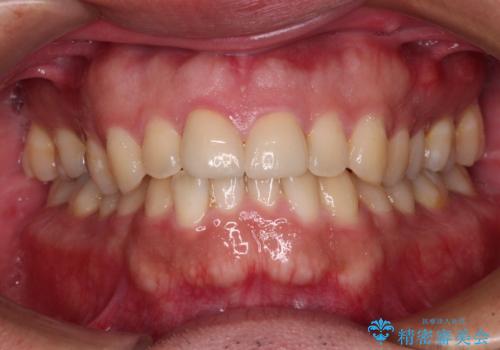

仮歯に置き換え、しみる感覚が改善されてことを確認された後に、オールセラミッククラウンにて補綴治療を行うこととしました。

術後の経過は良好でしたが、レントゲン写真にて神経が失活している時に認められる透過像のようなものが見られました。

神経の反応はあるので失活していないようですが、時間が経過すると衝撃による失活が起こることもあるため、定期的な経過観察が必要です。